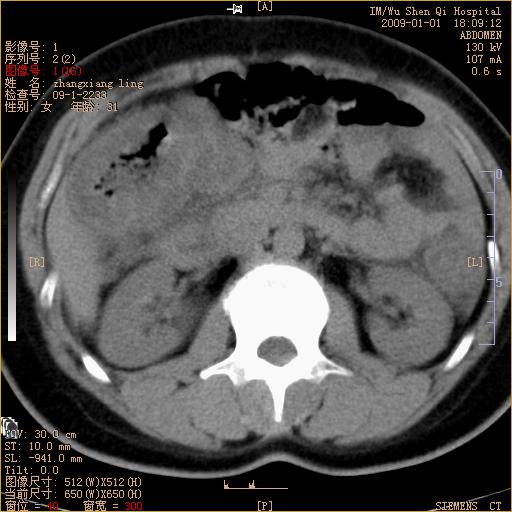

标题: CT17527:F31Y,腹痛伴血便9小时 [打印本页]

标题: CT17527:F31Y,腹痛伴血便9小时

升结肠肠壁不规则增厚,肠腔狭窄,考虑升结肠占位,建议增强扫描

升结肠肠壁不规则增厚,肠腔狭窄,考虑升结肠占位,建议增强扫描,不除外肠套叠.

升结肠肠壁不规则增厚,似呈同心圆改变,其有积液。结合病史首先考虑肠套叠伴肠壁坏死可能性大,结肠肿瘤待排。

患者已手术,结果肠系膜血栓形成肠坏死

结果:患者已手术,结果肠系膜血栓形成肠坏死。回过头再看局部肠壁增厚有分层(高密度坏死及低密度水肿)表现。